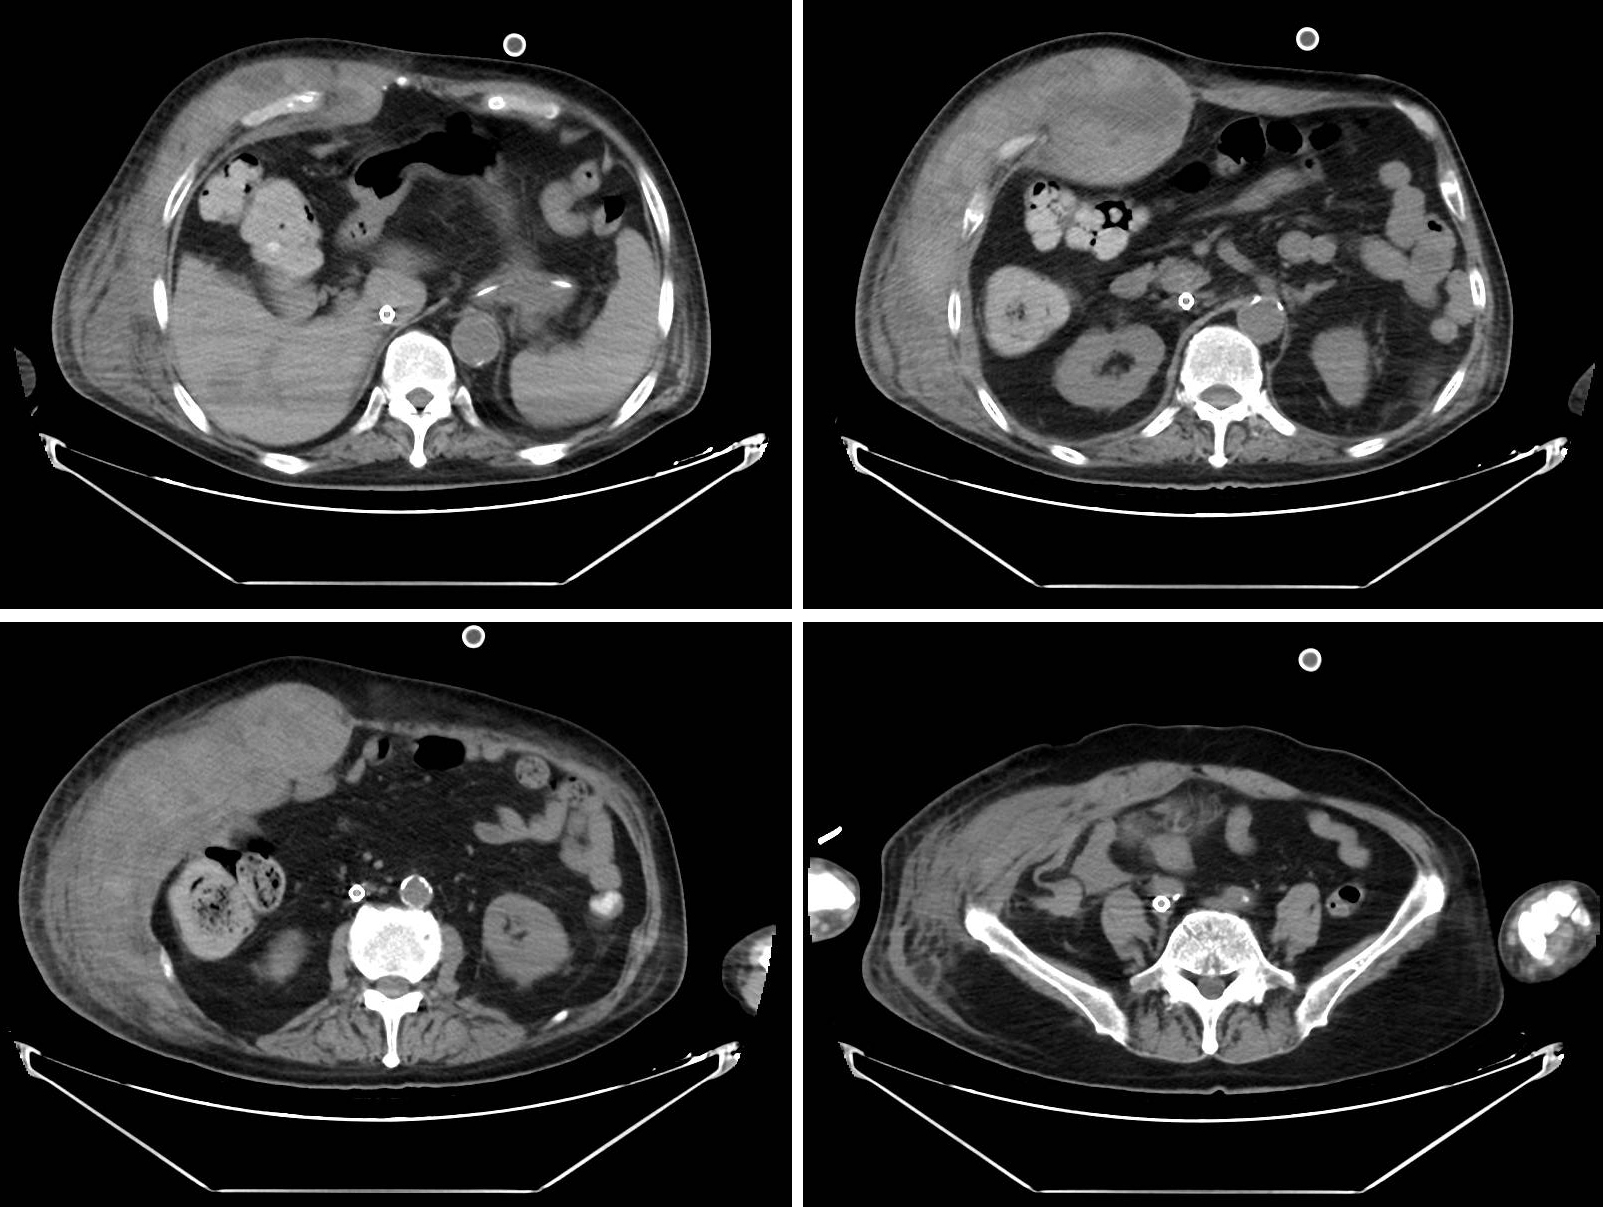

1 资料与方法患者男性,72岁,身高168 cm,体重85 kg,因“发热伴咳嗽6 d,呼吸困难1 d”由当地医院转入本院,患者最高体温38.2 ℃,咳嗽,少量黄脓痰,当地胸部CT提示两肺感染,给予积极抗感染治疗后患者病情进行性加重,1 d前出现呼吸困难,给予气管插管、呼吸机辅助通气后转入本院。既往2型糖尿病病史10年余,服用二甲双胍治疗,抑郁症病史12年余,服用盐酸文拉法辛胶囊,无烟酒不良嗜好。入院查体:体温37.4 ℃,脉搏109次/min,呼吸20次/min,血压116/60 mmHg(1 mmHg=0.133 kPa)。RASS评分−3分,双侧瞳孔等大等圆,直径2.0 mm,对光反射迟钝。颈软,经口气管插管,呼吸机容量控制通气[参数设置:VT 300 mL,FiO2 80%,R 20次/min,PEEP 10 cmH2O(1 cmH2O=0.098 kPa),I∶ E为1∶ 2],双侧呼吸音粗,可闻及湿啰音。心率109次/min,律齐,无明显杂音。腹部软,稍膨隆,压痛反跳痛无法配合,双下肢无水肿,肌力检查无法配合,双侧巴氏征阴性。入院时辅助检查:头颅CT未见明显异常;胸部CT提示两肺多发斑片影,两下肺为显著。入院诊断为重症肺炎、ARDS、2型糖尿病、抑郁症,接受了优化的有创机械通气联合俯卧位治疗,但是病情继续恶化,氧合指数(PaO2/FiO2) < 80 mmHg。10 h后患者接受了VV-ECMO支持(MAQUET公司,右股静脉21 Fr引出,右颈内静脉17 Fr回输),期间常规予以普通肝素抗凝并监测凝血,根据ACT联合APTT滴定肝素剂量,ACT目标150~180 s,APTT 40~60 s, 超过两者上限之一及时降低肝素剂量。ECMO运行期间保护性机械通气联合每日约16 h的俯卧位通气治疗,并充分镇静镇痛。第7日患者收缩压下降至90 mmHg以下,予以补液的同时急查血红蛋白从前一日的97 g/L降至62 g/L,未发现明显出血部位,考虑不排除胃肠道出血尚未排出体外可能,给予停止俯卧位通气、暂停抗凝同时予以禁食、输血、补液以及去甲肾上腺素维持循环等对症处理,但是血红蛋白仍不稳定。至第9日,共输注红细胞2 000 mL,查血红蛋白69 g/L,未见血便排出,进一步查体发现该患者肥胖的腹部右侧腹壁高于左侧,但皮肤未见瘀斑(图 1)。进行腹部CT检查,发现右侧腹壁软组织弥漫性增厚、渗出明显,见包裹性高密度影,高密度区CT值约45 HU,考虑腹直肌鞘血肿(图 2)。随之行血管造影发现远端腹壁上动脉细小分支见造影剂外溢,500~700 um明胶海绵颗粒“淋浴”灌注栓塞,再次造影未见明显造影剂外溢。继续抗凝,ACT目标140~160 s,APTT 35~45 s, 患者血流动力学稳定,第12日夹闭ECMO气源情况下,患者PaO2/FiO2已升至250 mmHg,撤除ECMO,第13日拔除气管插管,第35日患者康复出院。

| 右侧腹壁软组织弥漫性增厚、渗出明显,见包裹性高密度影,高密度区CT值约45 HU,考虑腹直肌鞘血肿 图 2 患者入院后第9日腹部CT |